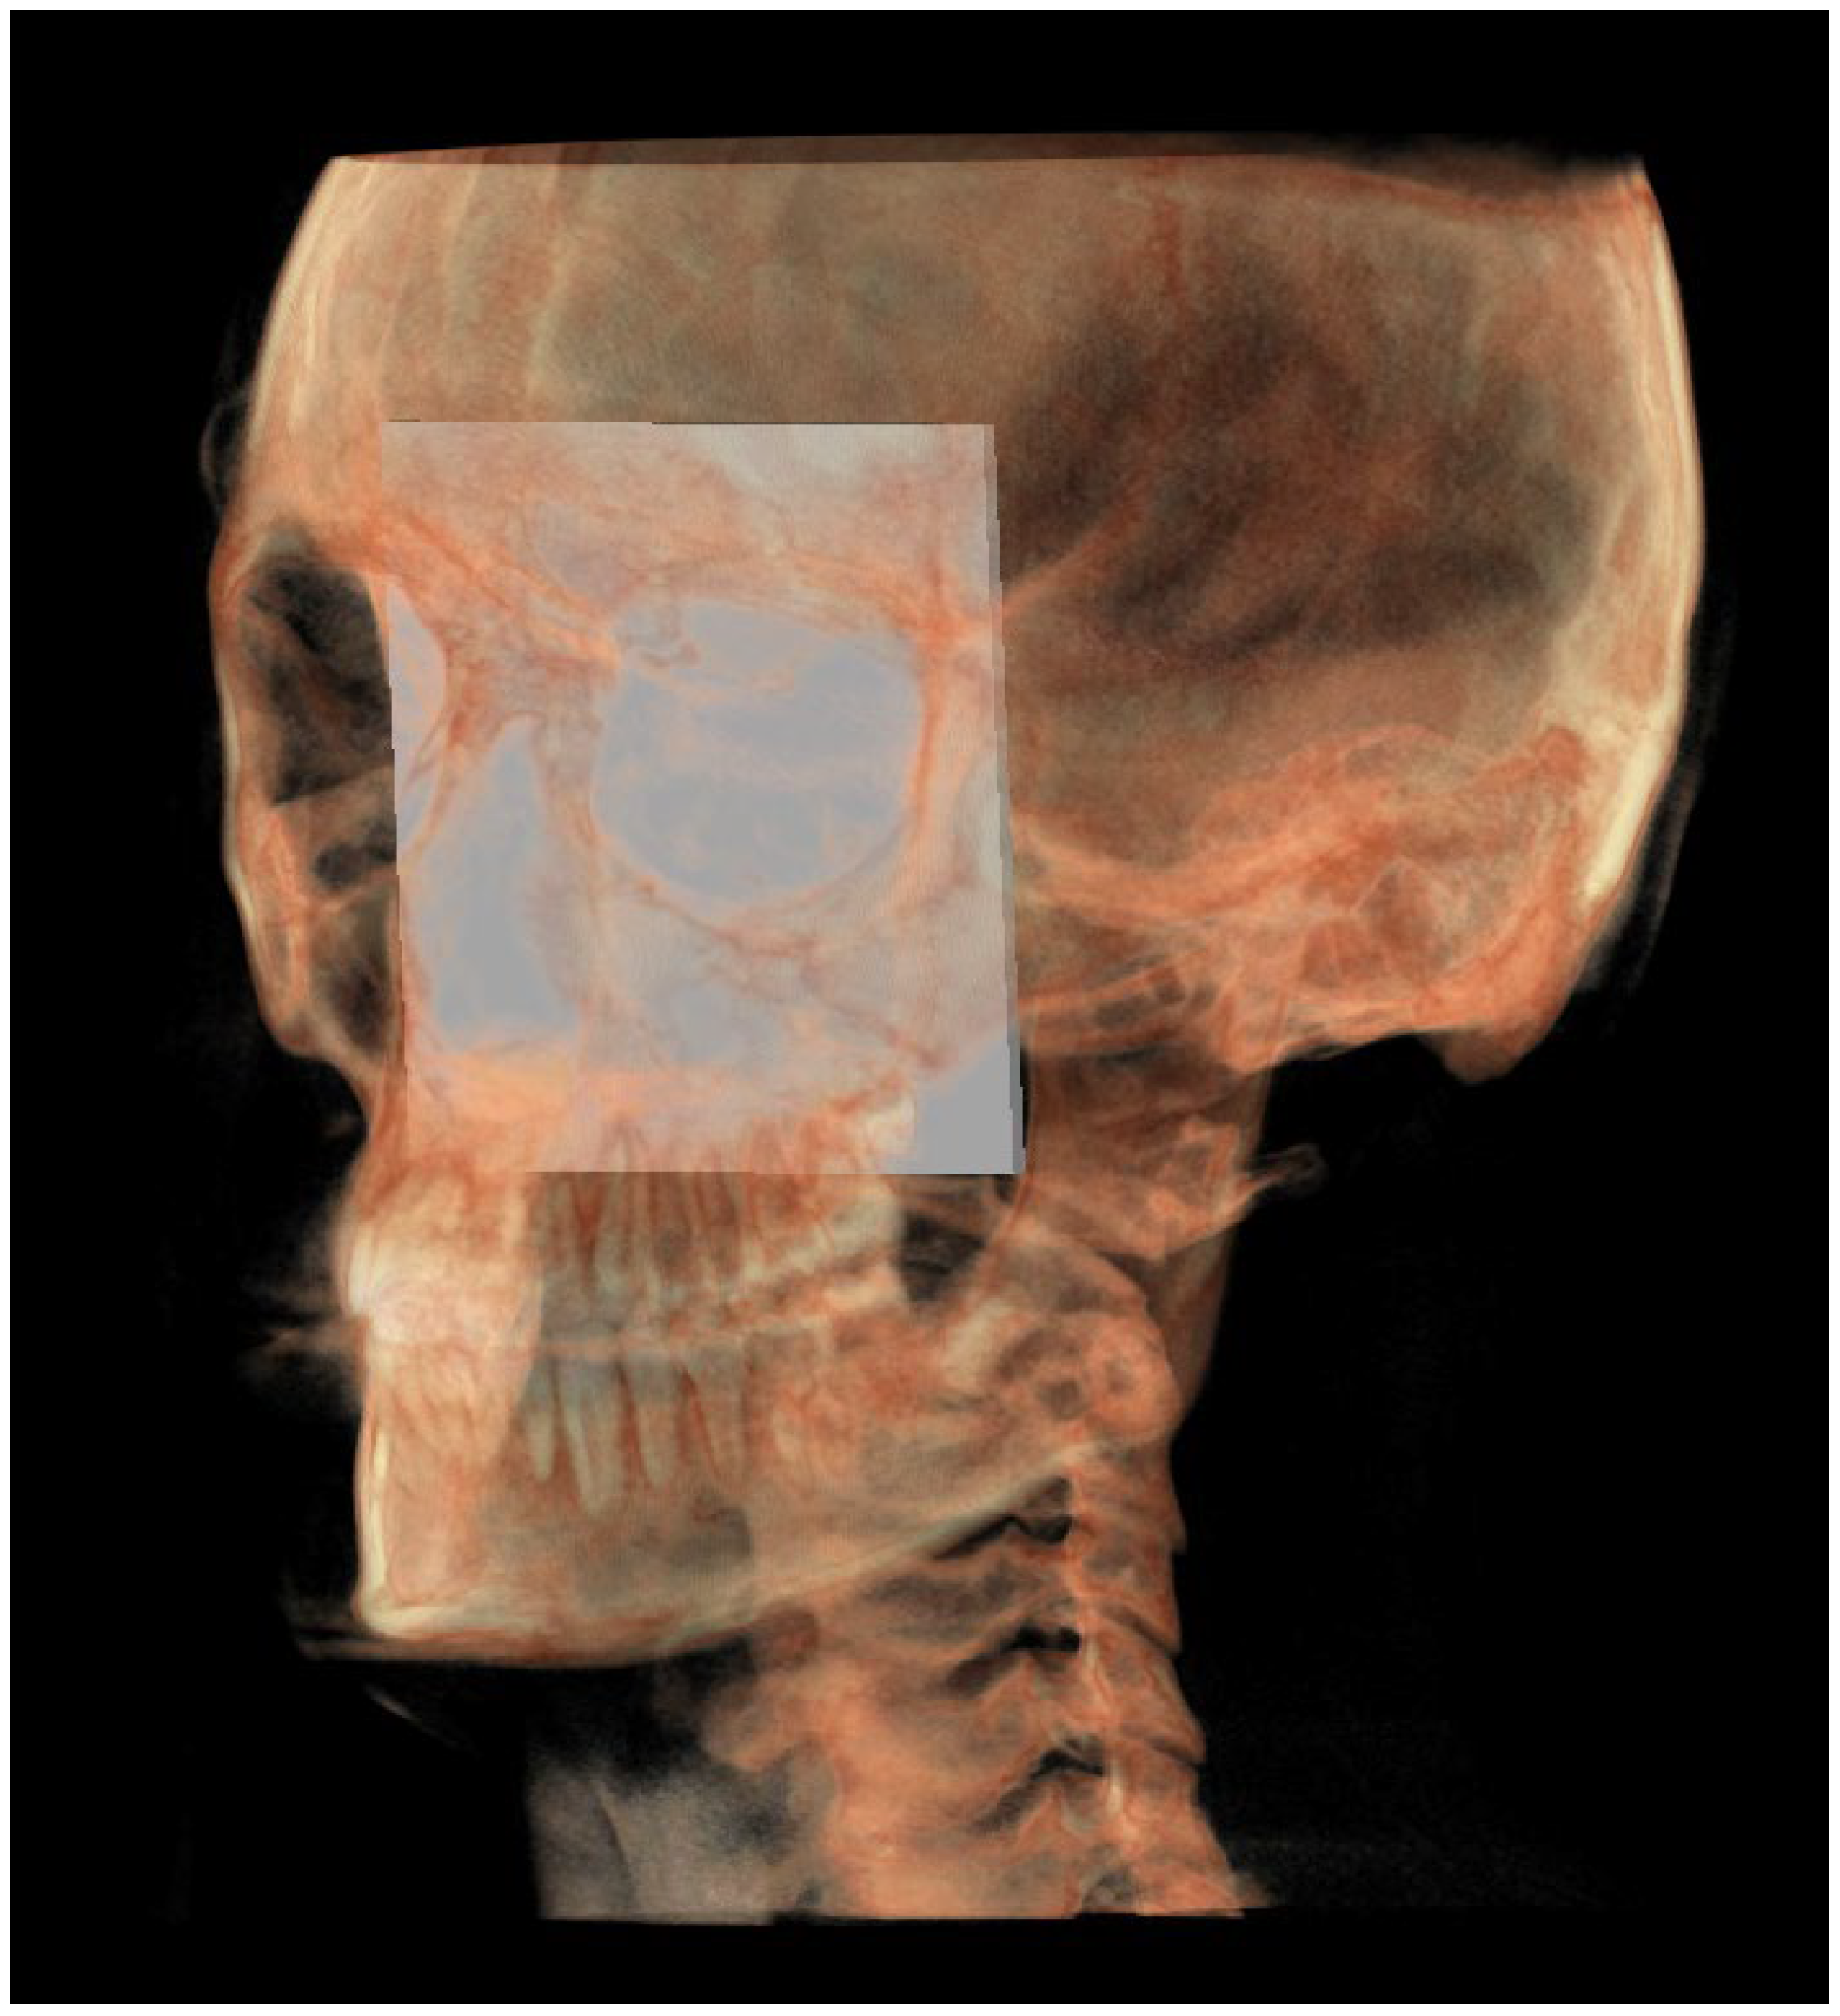

The MCF (Figure 3) was identified by the points middle cranial floor right side (rMCF) and middle cranial floor left side (lMCF) [12] and Basion (Ba);

Figure 3. Middle cranial floor.